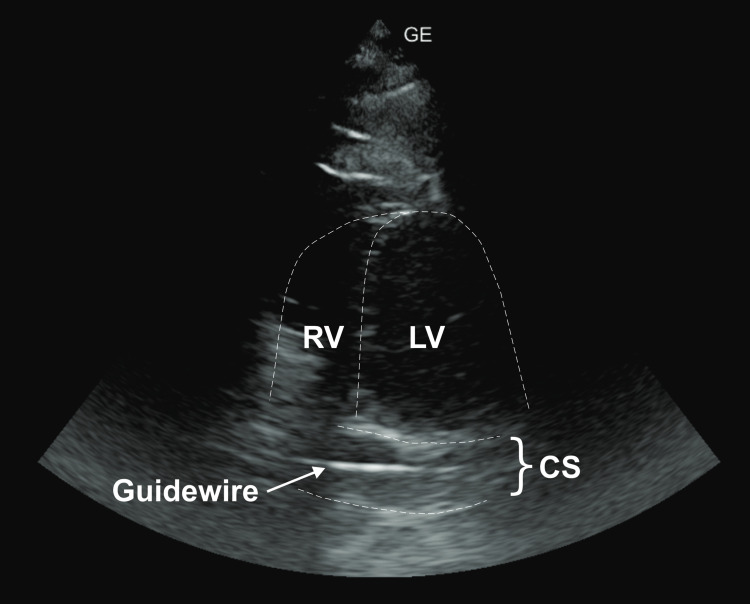

Guidewire loss is a rare complication of central venous catheterization. A 65-year-old male was hospitalized in a high-dependency unit for exacerbation of chronic obstructive pulmonary disease, pneumonia, erythrocytosis, and clinical signs of heart failure. Upon admission, after an unsuccessful right jugular approach, a left jugular central venous catheter was placed. The next day, chest radiography revealed the catheter located in the left parasternal region, with suspected retention of the guidewire, visually confirmed by the presence of its proximal end inside the catheter. The left parasternal location of the catheter and the typical projection of the guidewire in the coronary sinus, later confirmed by echocardiography, raised suspicion of a persistent left superior vena cava (PLSVC). Agitated saline injected into the left antecubital vein confirmed bubble entry from the coronary sinus into the right atrium. After clamping the guidewire, the catheter was carefully retrieved along with the guidewire without any complications. This is the first reported case of guidewire retention in PLSVC and coronary sinus. It underscores the potential causes of guidewire loss and advocates preventive measures to avoid this potentially fatal complication.